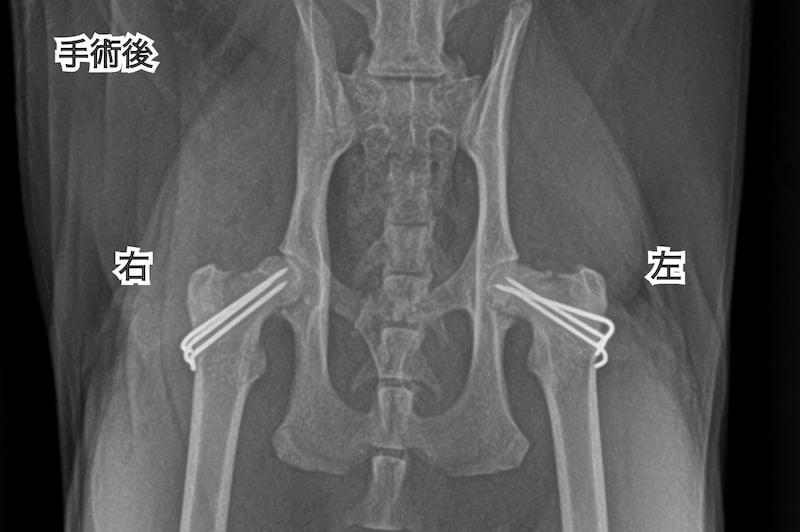

飼い主様と相談し、ピンニングによる骨折している右大腿骨の整復と併せて、いつ折れてもおかしくない左大腿骨のピンニングも行うことになりました。

こちらが手術後のレントゲン画像です。

翌日から猫は右後肢を軽く着地できるようになりました。

1ヶ月後には猫の歩様もほぼ正常化し、以前と同じ日常生活を送れるようになりました。